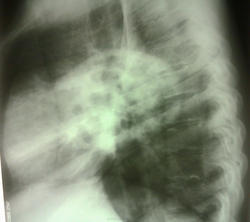

Больная доставлена СМП, флюроархива нет, больная асоциального вида, 1977 г.р. со слов больной болеет около месяца. температура 37.5 Интересует ваше мнение, коллеги...

необычная форма затемнения. Напоминает петли кишечника.

Мне тоже показалась кишка

Сперва подумал о грыже с "начинкой из кишки". Пневмония тоже может быть.

Однородная инфильтрация, множественные полости распада.. Пневмония наверное с присоединением какой-нибудь небанальной флоры

Возможно, формируется абсцесс.

Затемнение "вне анатомических границ". Покрутил бы за экраном, вывел бы на "контур", возможно получил бы осумкованный, или пневмоплеврит, возможно, с массивным обызвествлением костальной плевры.

А почему возникли мысли о "кишке"? Понимаю, что речь идет и крупных диафрагмальных грыжах, но куда деть четкий контур диафрагмы? Просветления на фоне инфильтрации очень напоминают полости распада при абсцедирующей верхнедолевой (язычковой) пневмонии, тем более что обзор брюшной полости не назначали, а значит и признаков патологии брюшной полости у пациентки нет? Не надо особо обольщаться асоциальностью, в наше время это не имеет уж такого большого значения!

тоже бросилось в глаза, что затемнение вне анатомических границ, за экраном покрутить не удалось, больная была "лежачая", очень истощенная.